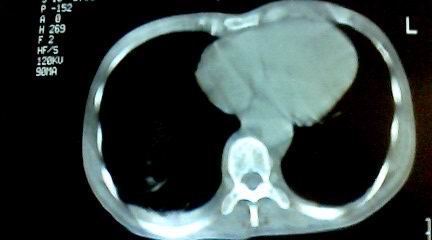

标题: CT25218:请教!胸部CT,胸8椎体骨质破坏,伴周围软组织肿。

患者,女41岁,肢体乏力。

两肺上叶继发性肺结核;胸椎结核并椎旁寒性脓肿形成。

胸椎结核并椎旁寒性脓肿形成。

支持,不过本人还要说有的占位和其它炎症也这样,你要是看到1000个这样的都报结核了,我保你其中必有错的